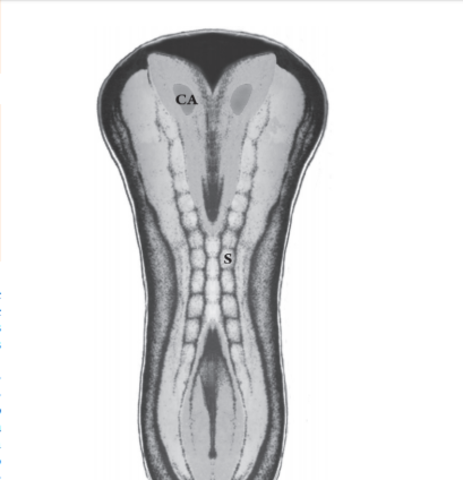

DESARROLLO DEL NERVIO ÓPTICO

- Los axones de las células ganglionares de la retina neurosensorial crecen hacia el pedículo o tallo óptico. De esta manera, la cavidad del tallo se va obliterando. La aparición de los axones en la futura papila se observa en embriones de 16 mm de longitud GL; 6,5 semanas de desarrollo, 44 días. Las células del pedículo óptico rodean cranealmente a estas fibras y a la arteria hialoidea

Día 37 de desarrollo; comienza el cierre de la hendidura embrionaria, debido al crecimiento de los bordes del pedículo óptico. Durante la semana 7 del desarrollo, se observa el quiasma óptico. En la región de la futura papila aparece una acumulación de glioblastos, esbozo de la membrana limitante de Elschnig y del menisco central de Kuhnt, separando las fibras del nervio óptico del vítreo secundario